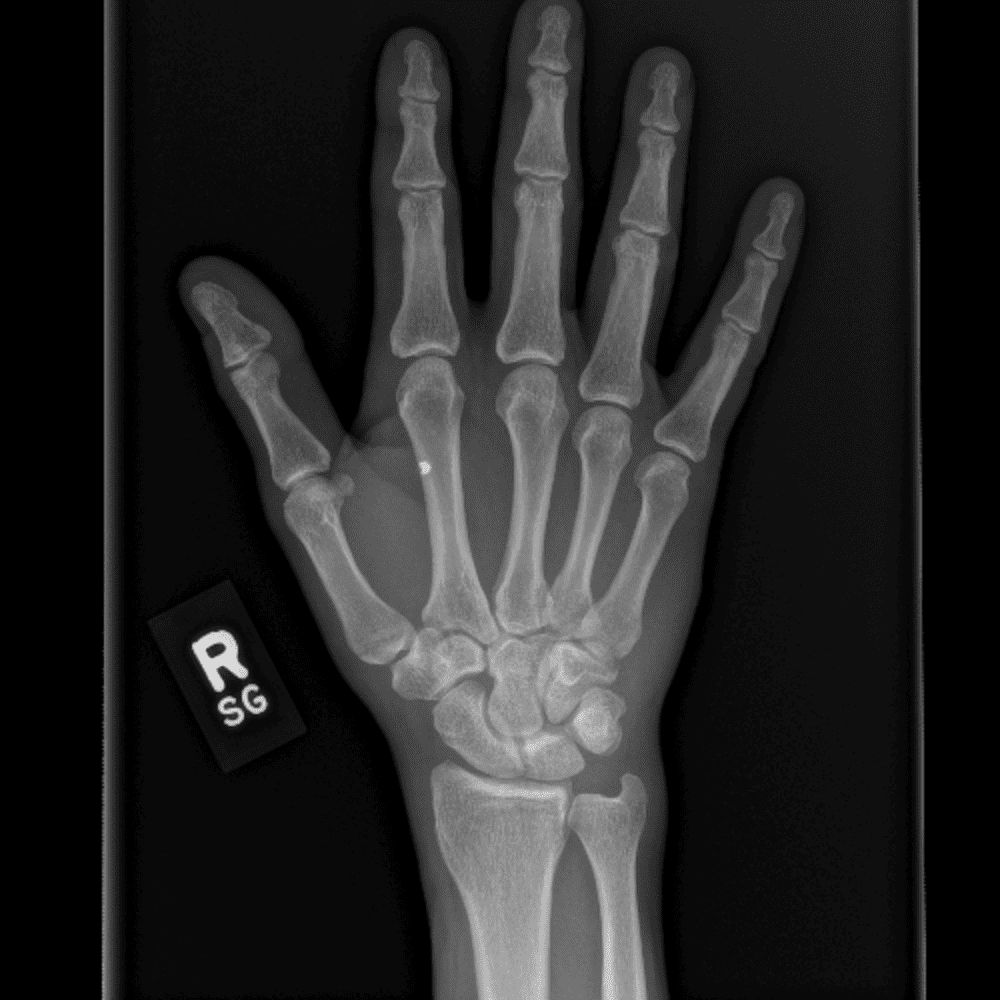

Simuliert den Dienst durch subtile oder schwierige Fälle und einige Normalbefunde.

30 Fälle